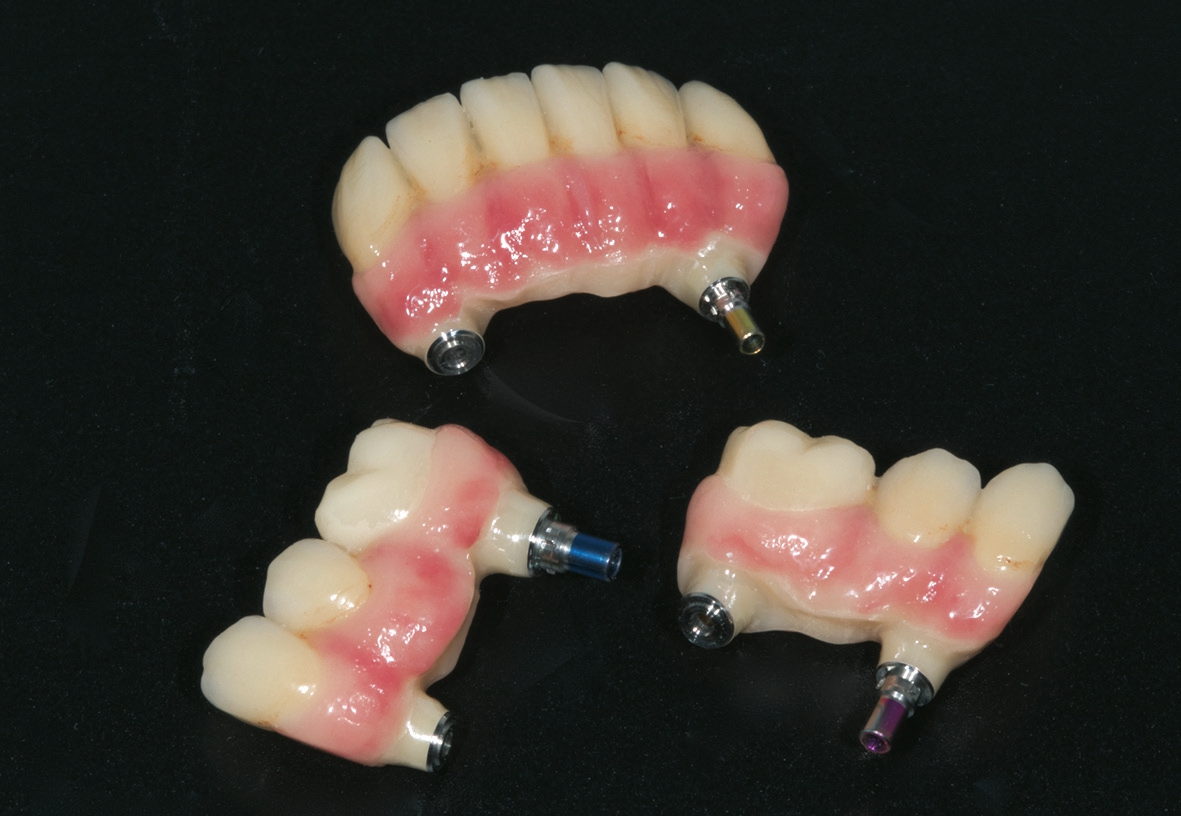

Bei reizlosem postoperativem Verlauf konnten die Implantate wie geplant nach drei Monaten freigelegt werden. Um das Emergenzprofil für die Prothetik möglichst optimal zu gestalten, kamen dabei sowohl zylindrische als auch wide body Gingivaformer zum Einsatz. Nach einer Heilungszeit von zwei Wochen für das Weichgewebe wurde der Patient für die prothetische Phase an die zuweisende Zahnarztpraxis (Dr. Andreas Karg, Lenggries) zurücküberwiesen. Dort wurde der Unterkiefer mit drei Brückensegmenten 46-44, 43-33, 34-46 definitiv versorgt. Zunächst erfolgte nochmals eine exakte zentrische Relationsbestimmung mit auf den Implantaten verschraubten Gerber-Stützstiftregistrat-Platten (Abb. 16). Anschließend wurden die Brückengerüste in CAD/CAM-Technik konstruiert und aus Zirkonoxid gefräst und individuell keramisch vollverblendet. Im Oberkiefer wurde zunächst ein auf provisorischen Abutments reversibel zementiertes Langzeitprovisorium aus PMMA mit glasfaserverstärkten Strängen (Targis Vectris) eingegliedert, um Phonetik, Ästhetik, Hygienefähigkeit und die Bisslage nochmals über eine Tragezeit von sechs bis neun Monaten zu evaluieren und falls notwendig letzte Korrekturen durchführen zu können (Abb.17-23). Danach ist die definitive Versorgung mit vier einzelnen Brückensegmenten in regio 16- 14, 13-11, 21-23 sowie 24-26 geplant.

Das implantatprothetische Konzept mit acht Oberkieferund sechs Unterkieferimplantaten wurde gewählt, um große Brückenspannen zu vermeiden. Durch die Implantatposition sind im Oberkiefer vier und im Unterkiefer drei jeweils kurzspannige Brücken realisierbar (16-14, 13-11, 21-23, 24-26, 36-34, 33-43, 44-46). Dies bringt Vorzüge hinsichtlich der Zahnersatz-Passung einerseits, erhöht aber auch die Reparaturfreundlichkeit im Falle eines Chippings o.ä. signifikant.

Bei Implantatversorgungen in beiden Kiefern ist das Problem von Chipping durch die fehlende physiologische Zahnbeweglichkeit einerseits, aber auch den fehlenden „occlusal sense“ andererseits eine große prothetische Herausforderung. Daher eignen sich hierfür entweder monolithische Konstruktionen oder die Verwendung von hochverdichtetem Komposit als Verblendungsmaterial in einem Kiefer. Bei monolithischen Restaurationen, z. B. aus Zirkonoxid, ist zwar das Chipping-Risiko ebenfalls minimiert, andererseits sind die hierbei entstehenden unphysiologisch hohen okklusalen Kräfte kritisch zu bewerten. Bei Patienten, bei denen funktionelle Parameter wie Bisslage und -höhe verändert wurden bzw. die von herausnehmbaren auf festsitzenden Zahnersatz umgestellt werden, ist darüber hinaus die Verwendung von Langzeitprovisorien sehr empfehlenswert, um evtl. noch erforderliche Feinanpassungen zu ermöglichen.